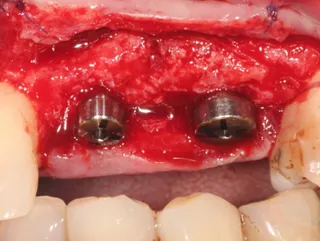

5a-b. Implants were placed away from the edge of the vestibular bone, 0.5 to 1.5 mm subcrestally, so that the implant collar lay 3 mm apical to the collar of the removable overdenture teeth. The design of the Axiom X3® implant limits insertion-related stresses in the bone and thus favors bone preservation. In this clinical situation of average bone density, the Axiom X3® drilling protocol is shortened without the need to use the final drill. Final insertion of each implant was carried out by hand using the ratchet wrench and primary stability was correct.

6a-b. Hand-tightening of Ø 4 mm healing screws for the incisors and Ø 5 mm healing screws for the premolars.